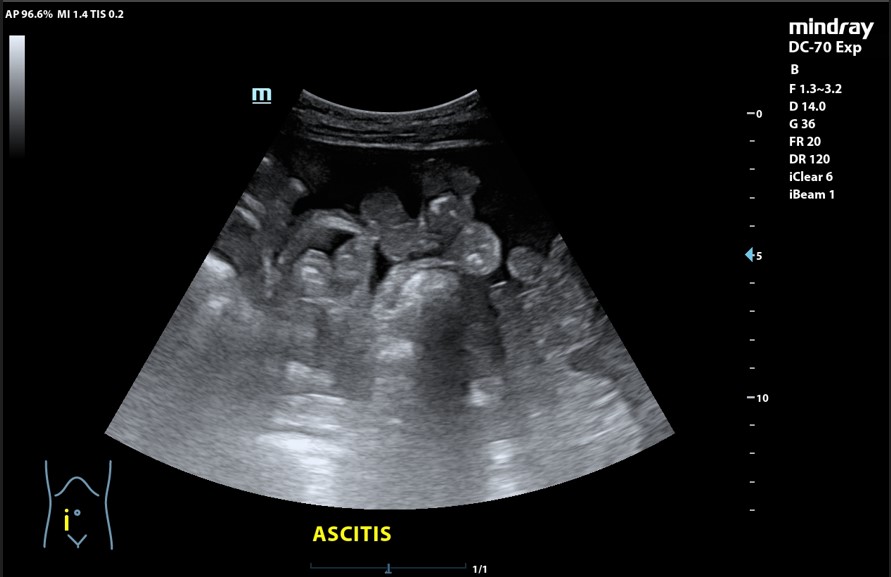

Presencia de 2 masas pélvicas bien delimitadas heterogéneas que captan Doppler, una de 5 cm de diámetro y otra ovalada de 10 cm de longitud. Líquido ascítico peritoneal, que también se observa alrededor del bazo y en espacio de Morrison. Derrame pleural derecho.